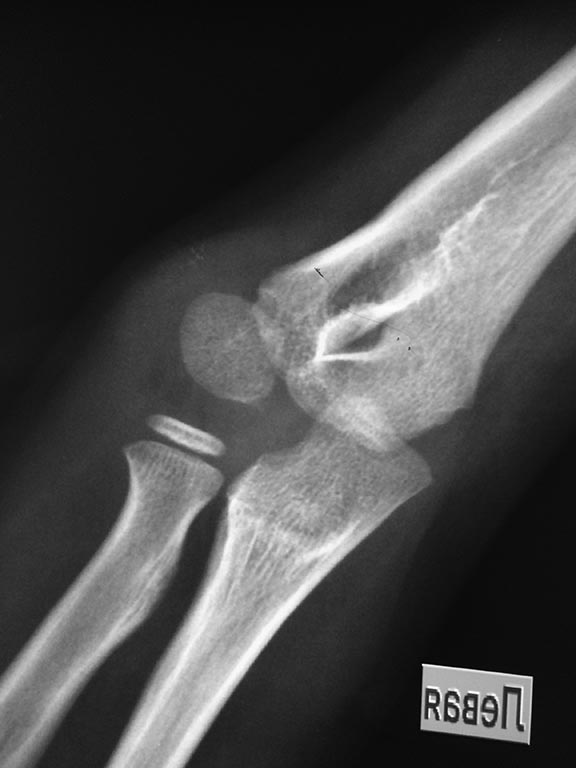

неправильно сросшийся перелом дистального конца левой плечевой кости |

Доброго времени суток Уважаемые учителя и коллеги!!!Больной 10 лет. Имеется неправильно сросшийся перелом дистального конца левой плечевой кости В примерно 1,5 годичном возрасте сломал руку и лечитлся консервативно! Сейчас имеется незначительная варусная деформация левого локтевого сустава примерно до 10 градусов. Функция сустава без дефекта. При разгибании имеется деформация незначительная (выступ) по наружной поверхности сустава. При сгибании деформация незаметна. Обязательно ли делать остеотомия корригирующую? Если да, в каком объеме? Снимок отправляю. Большое спасибо заранее!!